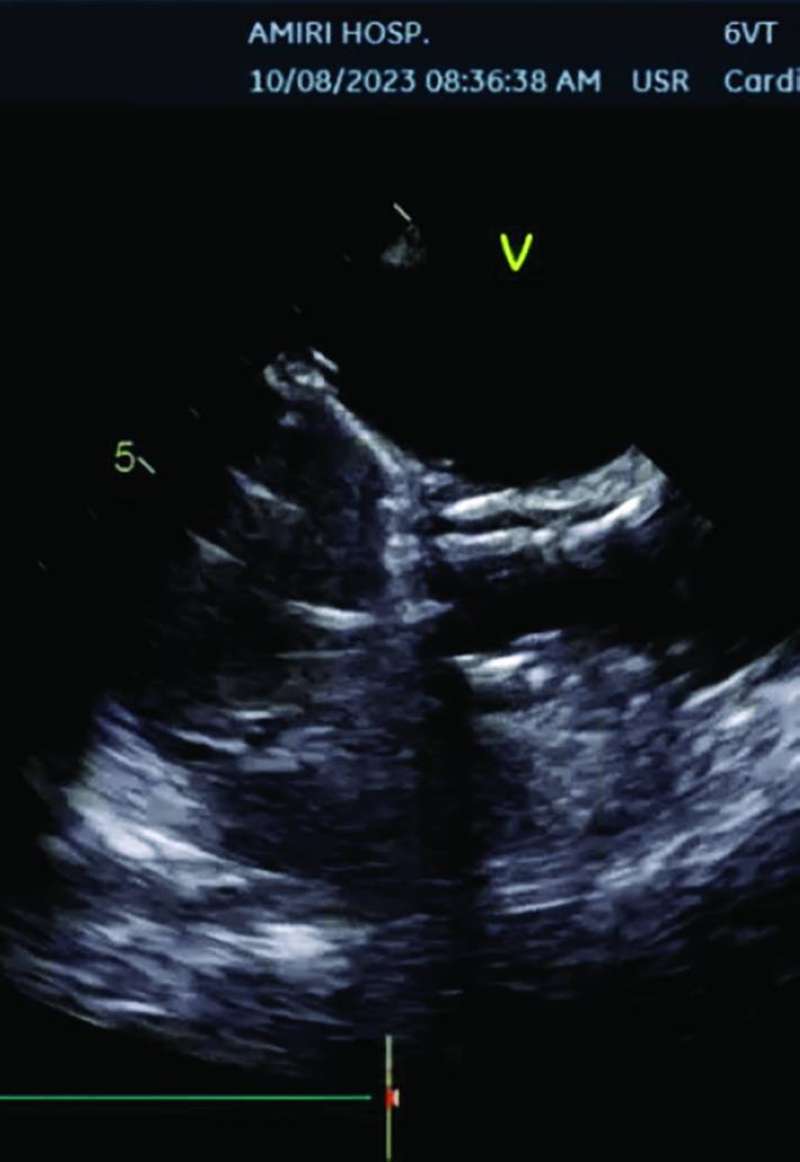

وأضاف «ساعدت التقنية الجديدة في الصمام، بوجود طبقة تساعد على ثباته بوضعه المحدد بدقة في هذه المسافة الضئيلة،على نجاح عمل تبديل الصمام. وقد تمت الاستعانه بسونار القلب عن طريق المريء وتقنية الإيكو ثلاثي الأبعاد (3D TOE) لتثبيت ووضع الصمام بدقة شديدة من دون التداخل مع شرفات الصمام الميترالي المعدني. وتعد هذه الحالة الأولى من نوعها في الشرق الأوسط، من الحالات النادرة عالمياً، التي يتم فيها تبديل الصمام الأورطي عن طريق القسطرة بوجود صمام ميترالي معدني باستخدام مثل هذه التقنيات الحديثة».